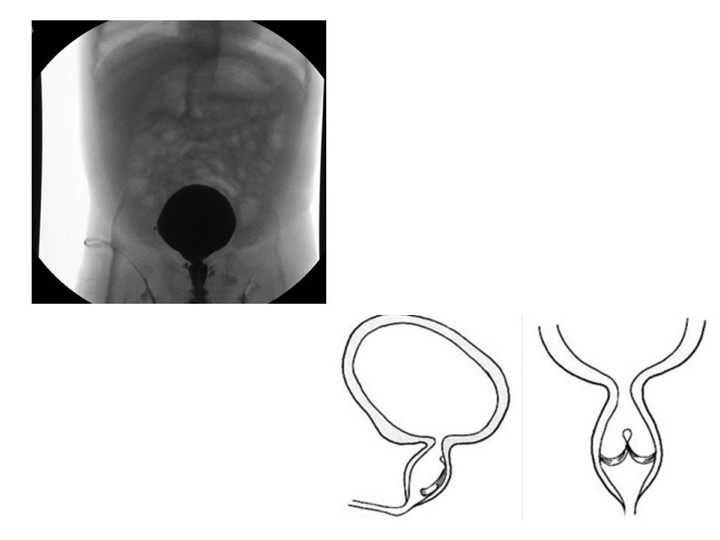

La classificazione di Young divide le valvole in 3 categorie: tipo I, tipo II (non ostruttivo) e tipo III. Il tipo I (90-95%dei casi) è rappresentato da una plica della mucosa uretrale a livello del verumontanum, che si dirige anteriormente e si biforca in due foglietti a livello dell’uretra bulbare. Questi possono estendersi verso l’alto fino ad occupare l’uretra per tutta la sua circonferenza. Solitamente le valvole sono fuse anteriormente con un’ apertura posteriore. Il tipo III può trovarsi a vari livelli dell’uretra posteriore ed è formato da una membrana ostruente circolare con una piccola apertura al centro.

All’ecografia prenatale segni sospetti per la presenza di valvole uretrali sono rappresentati dalla presenza di idroureteronefrosi bilaterale con vescica dilatata, iperecogenicità del parenchima renale, ed oligoidramnios. La vescica ha pareti molto spesse con possibili diverticoli e collo rigido. L’uretra prostatica è distesa ed i dotti eiaculatori possono essere dilatati alla cistografia (segno del ‘buco della serratura’). La gestione del neonato con VUP è, possibilmente, a carico di un team multidisciplinare che comprende neonatologi e pediatri della Terapia Intensiva Neonatale dove viene ricoverato il bambino, l’urologo ed il nefrologo pediatra. La diagnosi viene confermata dall’esecuzione di una cistografia minzionale (CUM) dopo la nascita. Creatinina, azotemia ed elettroliti vengono strettamente monitorati durante i primi giorni.